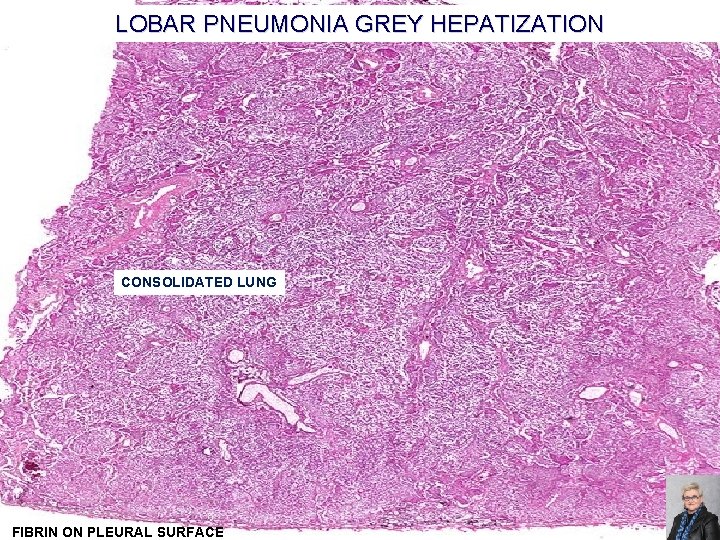

LOBAR PNEUMONIA; CLASSIC STAGES (AS SEEN IN PNEUMOCOCCAL PNEUMONIA) Congestion: �Heavy, boggy, red, hyperemic lungs with many bacteria but few neutrophils Red hepatization: �Massive confluent alveolar filling with RBCs, neutrophils, and fibrin Gray hepatization: �Disintegrating RBCs and fibrinopurulent exudate fill alveoli Resolution: �Macrophages mop up debris and normal function returns 59

LOBAR PNEUMONIA GREY HEPATIZATION CONSOLIDATED LUNG FIBRIN ON PLEURAL SURFACE 63

LOBAR PNEUMONIA, GREY HEPATIZATION ALVEOLI ARE FILLED WITH FIBRIN, EDEMA FLUID AND NEUTROPHILS 64